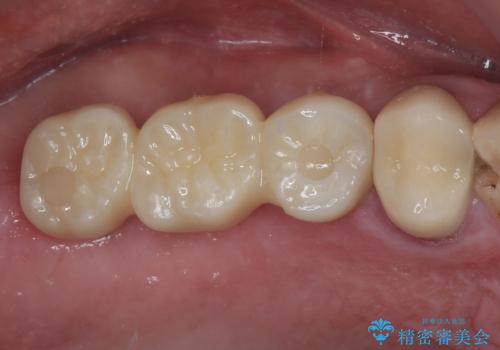

割れてしまった奥歯 抜歯即時埋入インプラントによる短期間治療